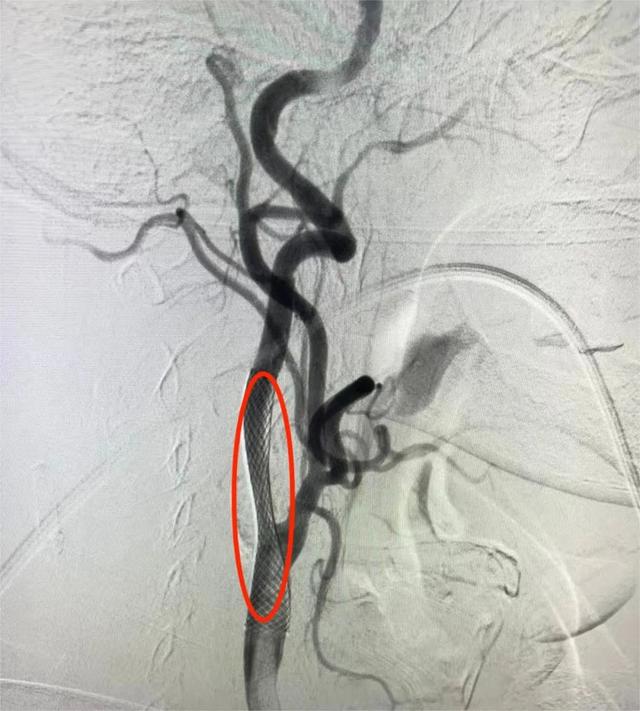

1月9日,桃源县人民医院神经内一科团队成功为一名复发脑梗死的颈动脉狭窄老人实施了“球囊扩张+支架植入术”,为老人解除了由颈动脉狭窄引起的一系列脑缺血症状,预防了大面积脑梗死的发生。

1.右侧颈内动脉C1段重度狭窄;

神经内一科主任谭辉副主任医师带领科室团队,对患者病情进行了详细的讨论与研究:患者“脑梗死”诊断明确,右侧颈内动脉C1段重度狭窄,为责任血管,CTP提示右侧大脑半球存在大片低灌注,内科治疗症状反复加重,有血管内介入治疗指征,无手术禁忌。

1月9日,神经内一科团队在局麻下为谢爷爷实施“右侧颈内动脉C1段狭窄球囊扩张+支架成形术”,手术顺利。术后即刻谢爷爷反应明显好转,可正确对答,左侧肢体肌力好转。